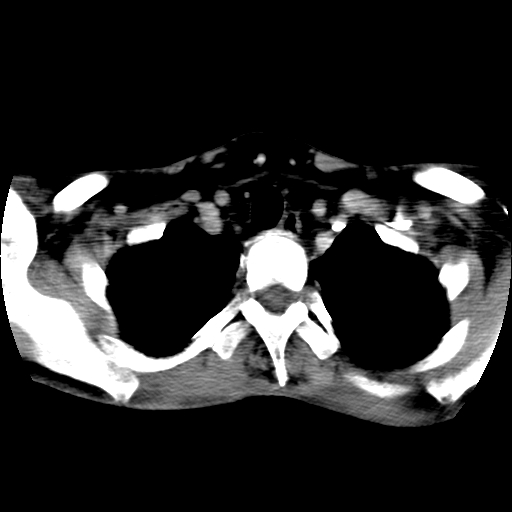

标题: CT24019:男,45岁,发现颈部肿物5个月。 [打印本页]

男,45岁,发现颈部肿物5个月,彩超示:双侧颈部及下颌部软组织增厚。

考虑双侧颈项部良性对称性脂肪增多症。

双侧颈项部脂肪沉积